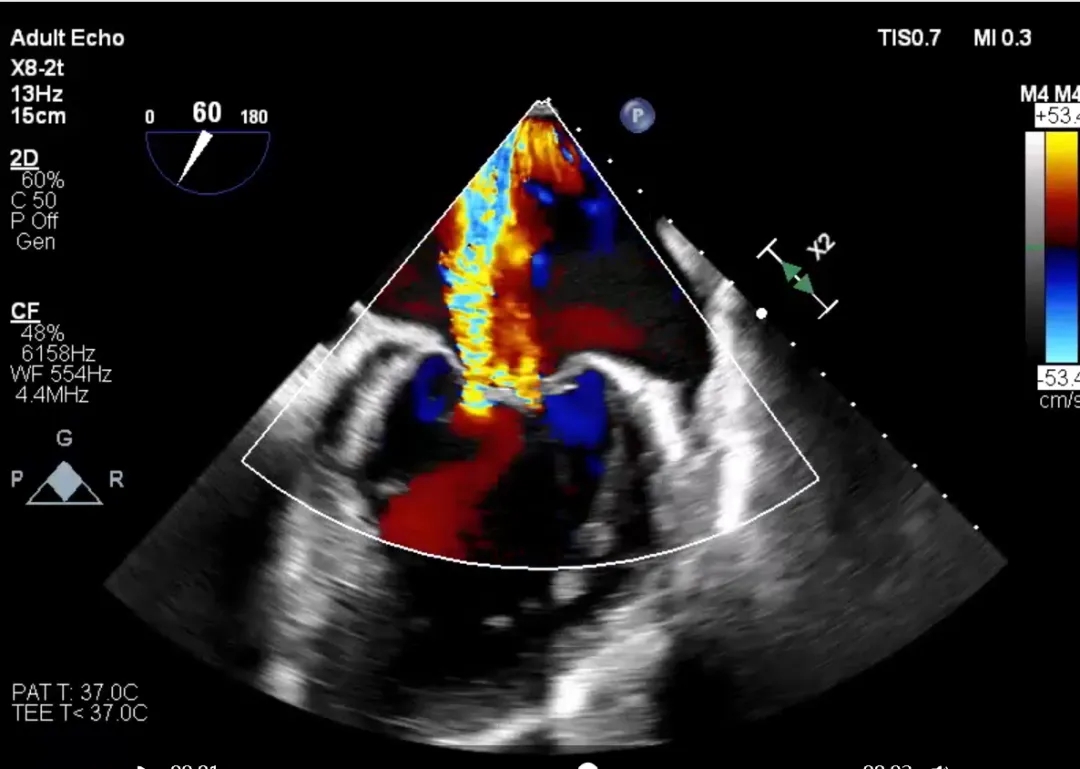

人工瓣膜植入后位置理想,无瓣周漏,无跨左室流出道压差。术后患者的二尖瓣反流明显改善,极大地缓解了患者的病痛并顺利出院。

术中,经左股动脉入路,在术前规划的DSA投射体位和超声引导配合下确认绕环导管初始深度,前进导丝绕过外交界-P3-P2-P1-内交界后,随血流跨主瓣返回升主动脉,在升主动脉使用snare抓捕。为了更充分地验证导丝成环轨道,术者在DSA与超声影像的共同指引下,清晰地观察到导丝均匀地向二尖瓣环与中心收紧。整个过程快速且一气呵成,术者顺利避开预估的所有Trap,为后续固定环的植入建立了确切的轨道。轨道建立后,固定环输送器沿着成环导丝经主动脉瓣推送至左心室,将固定环从输送器中推出,收紧导丝两端并完成固定环扣合。最后,在建立房间隔入路后,经右股静脉送入 HighLife瓣膜,在DSA的指引下先缓慢释放人工瓣膜心室端,后回拉输送器将瓣膜心室端与固定环贴紧二尖瓣环,并快速释放瓣膜心房端。在固定环的辅助下,人工瓣膜于二尖瓣瓣环平面完成自同轴展开释放,最后逐步撤出输送器。即刻超声评估提示二尖瓣反流完全消失,无瓣周漏,无左室流出道梗阻,人工瓣膜植入位置理想,形态良好。手术顺利结束。